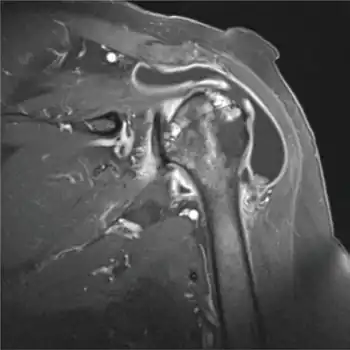

Imaging

X-rays may help visualize bone spurs, acromial anatomy and arthritis. Further, calcification in the subacromial space and rotator cuff may be revealed. Osteoarthritis of the acromioclavicular (AC) joint may co-exist and is usually demonstrated on radiographs.

MRI imagining can reveal fluid accumulation in the bursa and assess adjacent structures. In chronic cases caused by impingement tendinosis and tears in the rotator cuff may be revealed. At US, an abnormal bursa may show

- fluid distension,

- synovial proliferation, and/or

- thickening of the bursal walls.[11]

In any case, the magnitude of pathological findings does not correlate with the magnitude of the symptoms.[11]